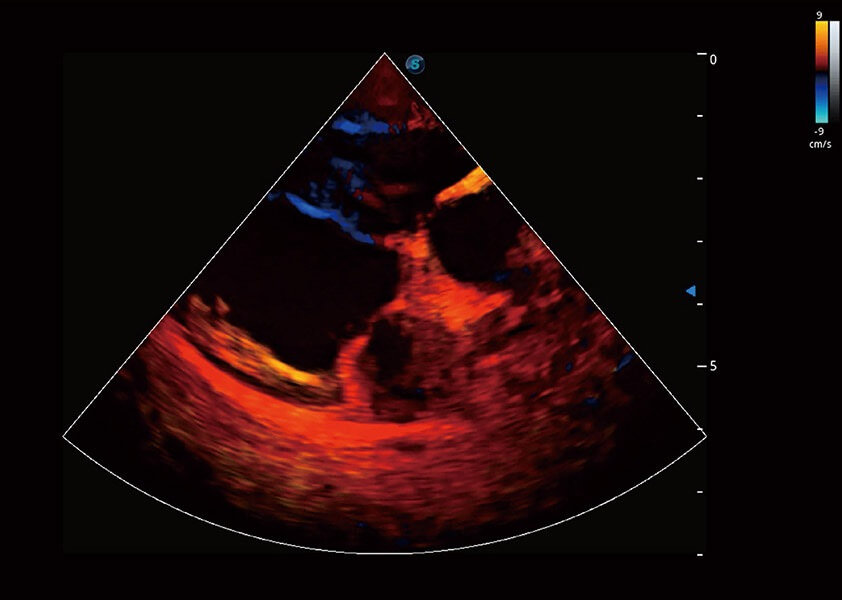

ProPet 60 作为一款高端台式动物超声设备,为动物医生的日常诊断提供了一系列贴合动物临床需求、解决临床实际问题的高级成像功能。凭借全系列高清探头,满足医生对腹部、心脏、生殖、浅表、肌骨等成像的所有需求,切实帮助您提升检查效率,提高诊断信心。

兽用彩色多普勒超声诊断系统

动物是人类最亲密的朋友和最值得信赖的伙伴。美狮贵宾会官网也一直致力于探索动物专用的超声影像解决方案。 全新推出的ProPet系列,是美狮贵宾会官网在动物超声影像智能化、专业化、精准化的一次跨越式革新。动物不能用言语来表述自己的不适,通过超声影像,ProPet系列搭建了动物医生与不同物种沟通的“桥梁”,为动物医生注入了“治愈之力”。